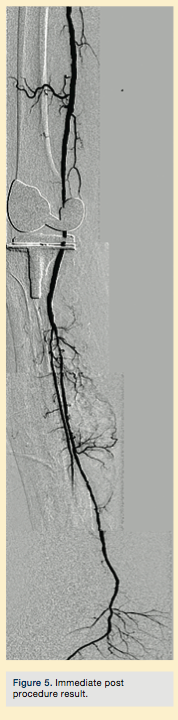

Peripheral angiography showed total occlusion of the right distal superficial femoral artery extending into the popliteal artery and into the trifurcation, with reconstitution of a peroneal and a posterior tibial. We attempted to obtain antegrade access to the lesions of the right infra-popliteal vessels (Figure 1). After failing to cross the lesion, we obtained retrograde access, puncturing from below the lesion through the posterior tibial artery near the ankle joint (Figure 2). Access was obtained and the lesion below the knee was crossed (Figure 3). Following this, the V-18 control wire (Boston Scientific) was snared from above, a CXI support catheter (CSI) was backloaded over the wire, and an antegrade Viperwire (CSI) was then placed, with removal of the retrograde sheath and wire. Atherectomy was performed with the 1.5mm Stealth 360° orbital atherectomy device (CSI) followed by balloon angioplasty with Cook, Sterling (Boston Scientific), and Chocolate (Cordis) balloon catheters. After angioplasty, significant improvement in luminal gain was noted at the expense of a dissection (Figure 4). We chose to place a Zilver PTX drug-eluting stent (Cook) within the distal superficial femoral and popliteal artery segment (Figure 5). After the procedure, the patient’s wounds completely healed. An angiogram 3 months later was performed, showing the vessels to be widely patent (Figure 6). The patient sent us a video of himself finally walking, and without pain (Video 1; online).